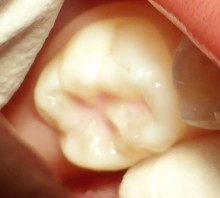

溝に、シーラントを入れます。

そして 青い光を当てます。

この ひかりでピンク色のシーラントは

固って白くなります。